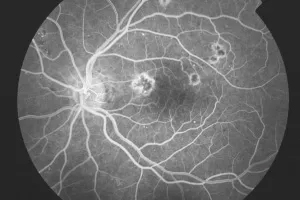

2. Fluoreszeinangiographie

Dies ist eine bewährte Untersuchungsmethode zur Darstellung der normalen und krankhaften Kreislaufverhältnisse von Aderhaut, Netzhaut und Sehnerv. Es wird der zeitliche Ablauf des Einströmens und Ausströmens eines speziellen Farbstoffes photographisch erfasst und digitalisiert. Dieser Stoff wird in die Armvene injiziert. Durch die Injektion verteilt sich dieser gelbe Farbstoff im gesamten Körper, auch in den Gefäßen im Auge.

Fluoreszeinangiographie – Augenärztliche Gemeinschaftspraxis | Dr. Heuring, Dr. Jung & Kollegen

Normalbefund der Gefäßdarstellung

fortgeschrittene AMD-Spätphase